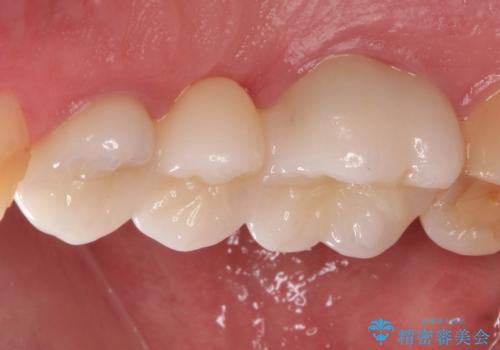

以前は保険治療で作られた金属のブリッジを装着されていましたが、オールセラミックブリッジを装着することにより、審美的にも改善されました。